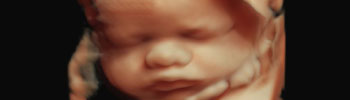

Ecografia 4D

Il Centro Medico Aricidiacono offre ai tutti i suoi pazienti la prima sonda elettronica 4D a matrice curva disponibile sul mercato! Tale macchina è in grado di offrire velocità volumetriche ultrarapide, formati di imaging flessibili ed eccellente risoluzione, per applicazioni che vanno dagli esami ostetrici di routine fino alla complessa ecocardiografia fetale